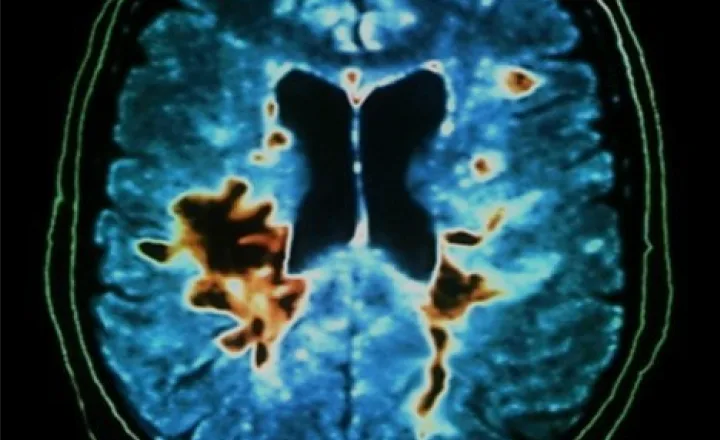

Multiple Sclerosis (MS) is a chronic neurological condition characterized by immune-mediated inflammation affecting the central nervous system. Regenerative medicine explores MSCs and exosomes therapy as supportive biological approaches to assist immune balance and regulate inflammatory pathways.

Multiple Sclerosis (MS) is a chronic neurological condition characterized by immune-mediated inflammation that affects the protective covering of nerve fibers within the central nervous system. The condition can influence mobility, coordination, sensory perception, and overall neurological function in varying degrees from person to person. In regenerative medicine, umbilical cord–derived mesenchymal stem cells (MSCs), often combined with exosomes therapy, are increasingly explored as supportive biological approaches aimed at assisting immune balance, regulating inflammatory pathways, and encouraging cellular communication under medical supervision.

Multiple Sclerosis involves immune-related activity that influences nerve signaling efficiency within the brain and spinal cord. Symptoms and progression patterns vary widely and may include fatigue, muscle weakness, coordination differences, and sensory changes. Because each individual experiences MS differently, multidisciplinary management approaches are commonly recommended to support long-term neurological function and quality of life.